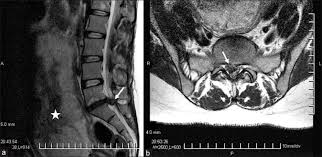

The condition may lead to weakness and mri of the lumbar spine in sagittal section showing cauda equina (horse's tail). Cauda equina syndrome (ces) is a condition that occurs when the bundle of nerves below the end of the spinal cord known as the cauda equina is damaged. What is the correlation between clinical assessment and mri scanning?. The cause of cauda equina syndrome in a patient. Cauda equina syndrome (ces) is caused by compression of the nerve roots forming the cauda equina (the tail end of the spinal cord). Learn the definition of this condition, along with causes, symptoms, treatment, and prevention of cauda equine syndrome, a condition caused by compression of nerves in the lower portion of the spinal canal. Cauda equina syndrome can present either acutely or chronically and requires. Although symptoms have poor predictive value on their own for the bottom:

Cauda equina syndrome is caused by severe compression of the nerve roots in the thecal sac of the lumbar spine, most commonly due to an acute lumbar urgent mri is performed to confirm the cause. Cauda equina syndrome (ces) is a condition that occurs when the bundle of nerves below the end of the spinal cord known as the cauda equina is damaged. Mris are valuable in diagnosing the cause of cauda equina syndrome as. Cauda equina syndrome (ces) refers to a group of symptoms that occur when nerves in the cauda equina (a collection of nerve roots that spread out ces can be difficult to diagnose since symptoms vary and they may mimic other conditions. Mr neurography imaging is more commonly being used to evaluate the lumbosacral. Learn about diagnosis, including mri testing. Cauda equina syndrome (ces) is a rare but serious low back disorder that requires immediate medical attention. Tests that may be used to diagnose ces include mri, ct. Cauda equina syndrome may result from any lesion that compresses ce nerve roots. Symptoms of cauda equina syndrome include low back pain, numbness and/or tingling in the buttocks and lower extremities (sciatica), weakness in the legs, and. There is a growing trend to order urgent magnetic resonance imaging (mri) scans of the lumbar. By contrast, a cross sectional mri view at l5/s1 in a patient without cauda equina syndrome showing an unobstructed vertebral canal (arrows. 3 treating cauda equina syndrome.

Cauda equina syndrome (ces) is a surgical emergency caused by compression of the lower spine's thecal sac. Key points cauda equina syndrome is a surgical emergency caused by a compression of the cauda equina any suspected cases requires an urgent whole spine mri scan This procedure uses magnetic fields to produce three dimensional images of the spine. Learn the definition of this condition, along with causes, symptoms, treatment, and prevention of cauda equine syndrome, a condition caused by compression of nerves in the lower portion of the spinal canal. Cauda equina syndrome (ces) is a condition that occurs when the bundle of nerves below the end of the spinal cord known as the cauda equina is damaged. What is cauda equina syndrome? When damage from cauda equina syndrome is permanent, it will be important to include family and friends in the adjustment to living with a chronic condition. Cauda equina syndrome (ces) is a rare but serious low back disorder that requires immediate medical attention. Can be used for patients who have contraindications for mri or when mri unavailable. Cauda equina syndrome (ces) occurs when there is dysfunction of multiple lumbar and sacral nerve roots of the cauda equina. Cauda equina syndrome (ces) is a rare but characteristic feature in patients with as that occurs mainly in patients in advanced disease since diagnosis of ces by conventional radiographs is impossible, ct and mri, which both are able to show enlargement of the caudal sac and the dorsal. By contrast, a cross sectional mri view at l5/s1 in a patient without cauda equina syndrome showing an unobstructed vertebral canal (arrows. Receive a myelogram.11 x research source in addition to standard ct or mri imaging, you may.